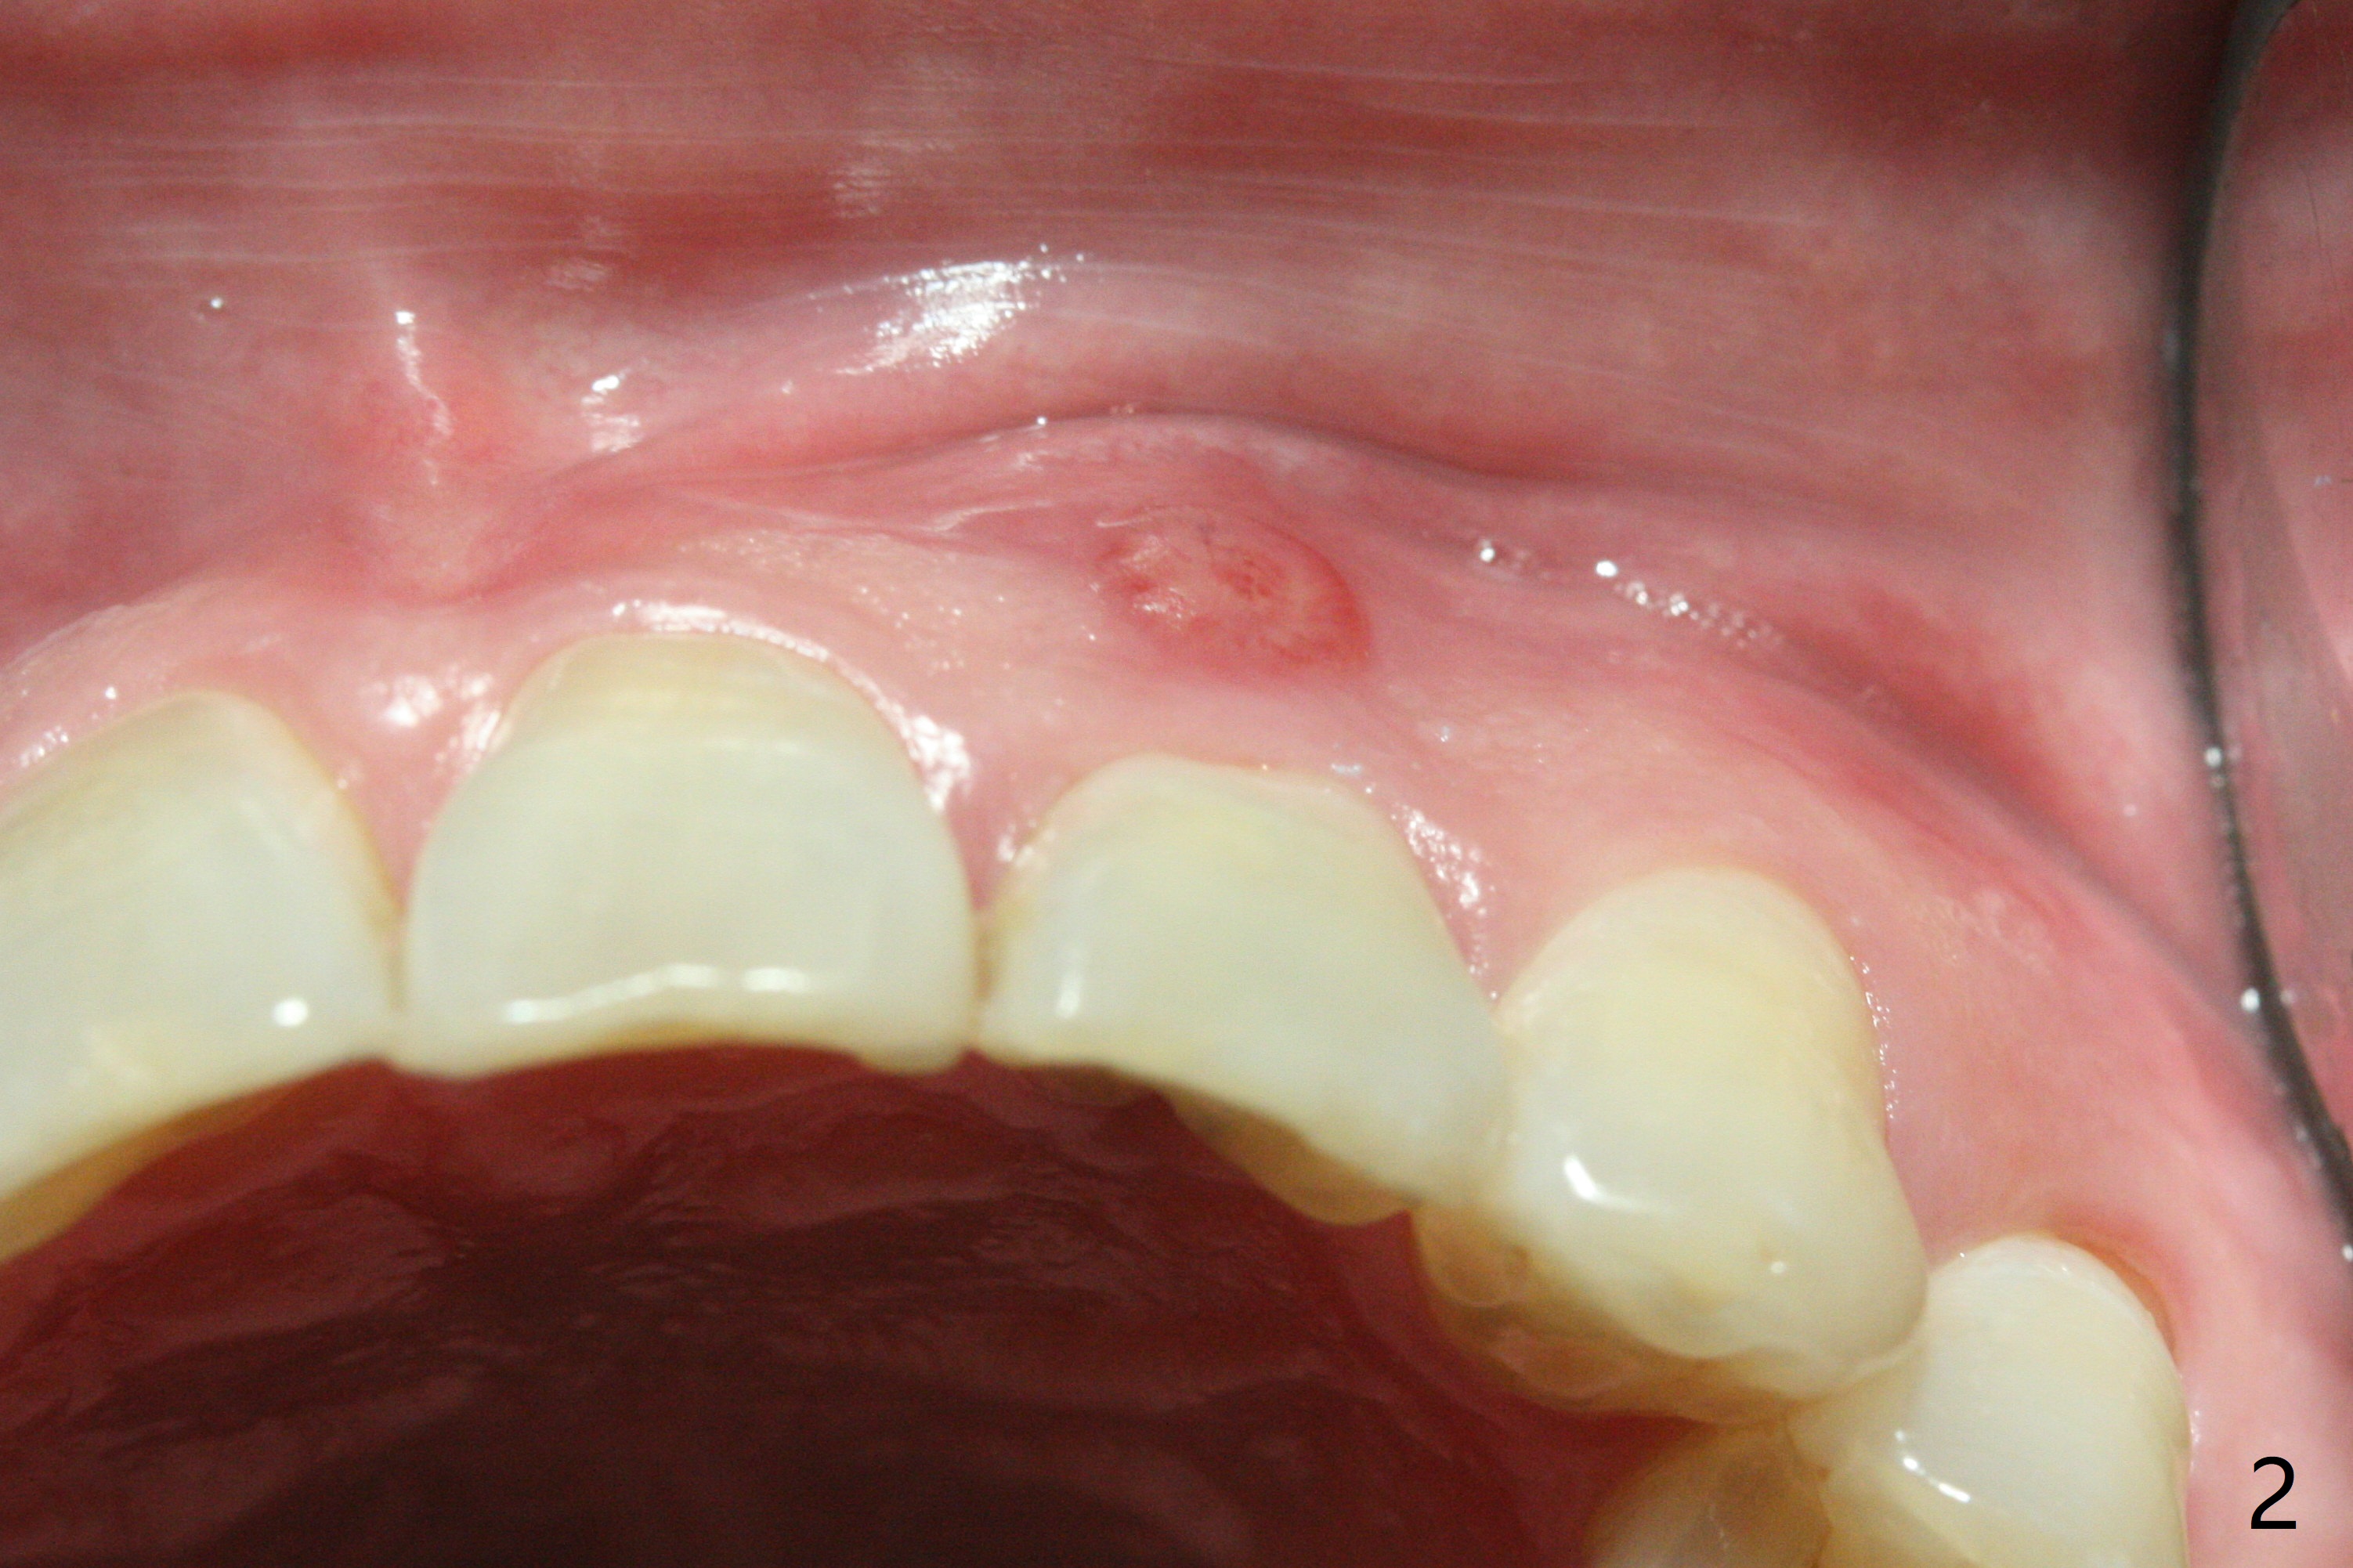

病人回来带来瘘道(图一),不过不会增加难度,病牙去除,它便自动消失。尽管颊侧骨壁完全失去,颊侧牙龈仍丰满(图二),为什么呢?第一,因为粗大牙根存在,第二两旁牙齿,牙槽骨撑着帐篷(侧切牙颊侧牙龈),第三,牙冠。为了防止术后牙龈塌陷,尽量不切开,即刻放置植体(牙根);由于前牙缘故,这次植体不能很大,所以植骨必须过度(over grafting),最后即刻制作临时牙冠,撑住牙龈。这就是所谓每个人进入角色。这个牙根有一种先天性畸形:dens in dent (图三(腭侧观):箭头)。尽管腭侧牙根畸形,腭侧骨壁吸收临床上并不严重,所以钻洞仍偏腭侧。当预定最后钻头还在钻洞时,填入大量粘性骨块(图四:*),细长植体还没有完全卡入鼻底(图五),最后好像可以(图六,七)。植体,骨粉入位(图八),最后临时牙冠出场(图九)。尽管植体小,术后一周临时牙冠仍然可以维持牙龈原有形状(emergency profile,图十:箭头(*:树脂强化牙冠固定))。图十一以不同角度显示瘘道缩小。术后三周取出有些松动的临时牙冠,骨粉虽然还没有被肉芽组织整合,但是显得正常,周围牙龈健康(图十二)。术后4个月牙龈形态正常(图十三),没有触痛;颊侧骨板轻度凹陷(图十四);骨粉仍在原位(图十五)。术后7个月骨粉仍在原位(图十五,十六,但是冠部密度减低(可能骨粉流失,需要牙周或者树脂敷料保护)),没有螺纹暴露。但是牙冠边缘暴露,说明牙龈收缩(图十七,与图十三对比),颊侧骨板仍塌陷(图十八)。插入龈线取得多个目的:修整基台边缘,取模,颊侧牙龈推向颊侧,有利于即将衬里牙冠龈缘进入龈下(图十九)。取模后牙冠边缘(图二十:<)衬里,然后修整,变窄,以便插入龈下,促进颊侧牙龈下降(图二十一,二十二)。术后8个月牙冠粘固前牙龈健康(图二十七,八),牙冠(图二十九)固位后,病人满意(图三十),咬合调整(图三十一),注意腭侧粘固粉流出通道(<)。